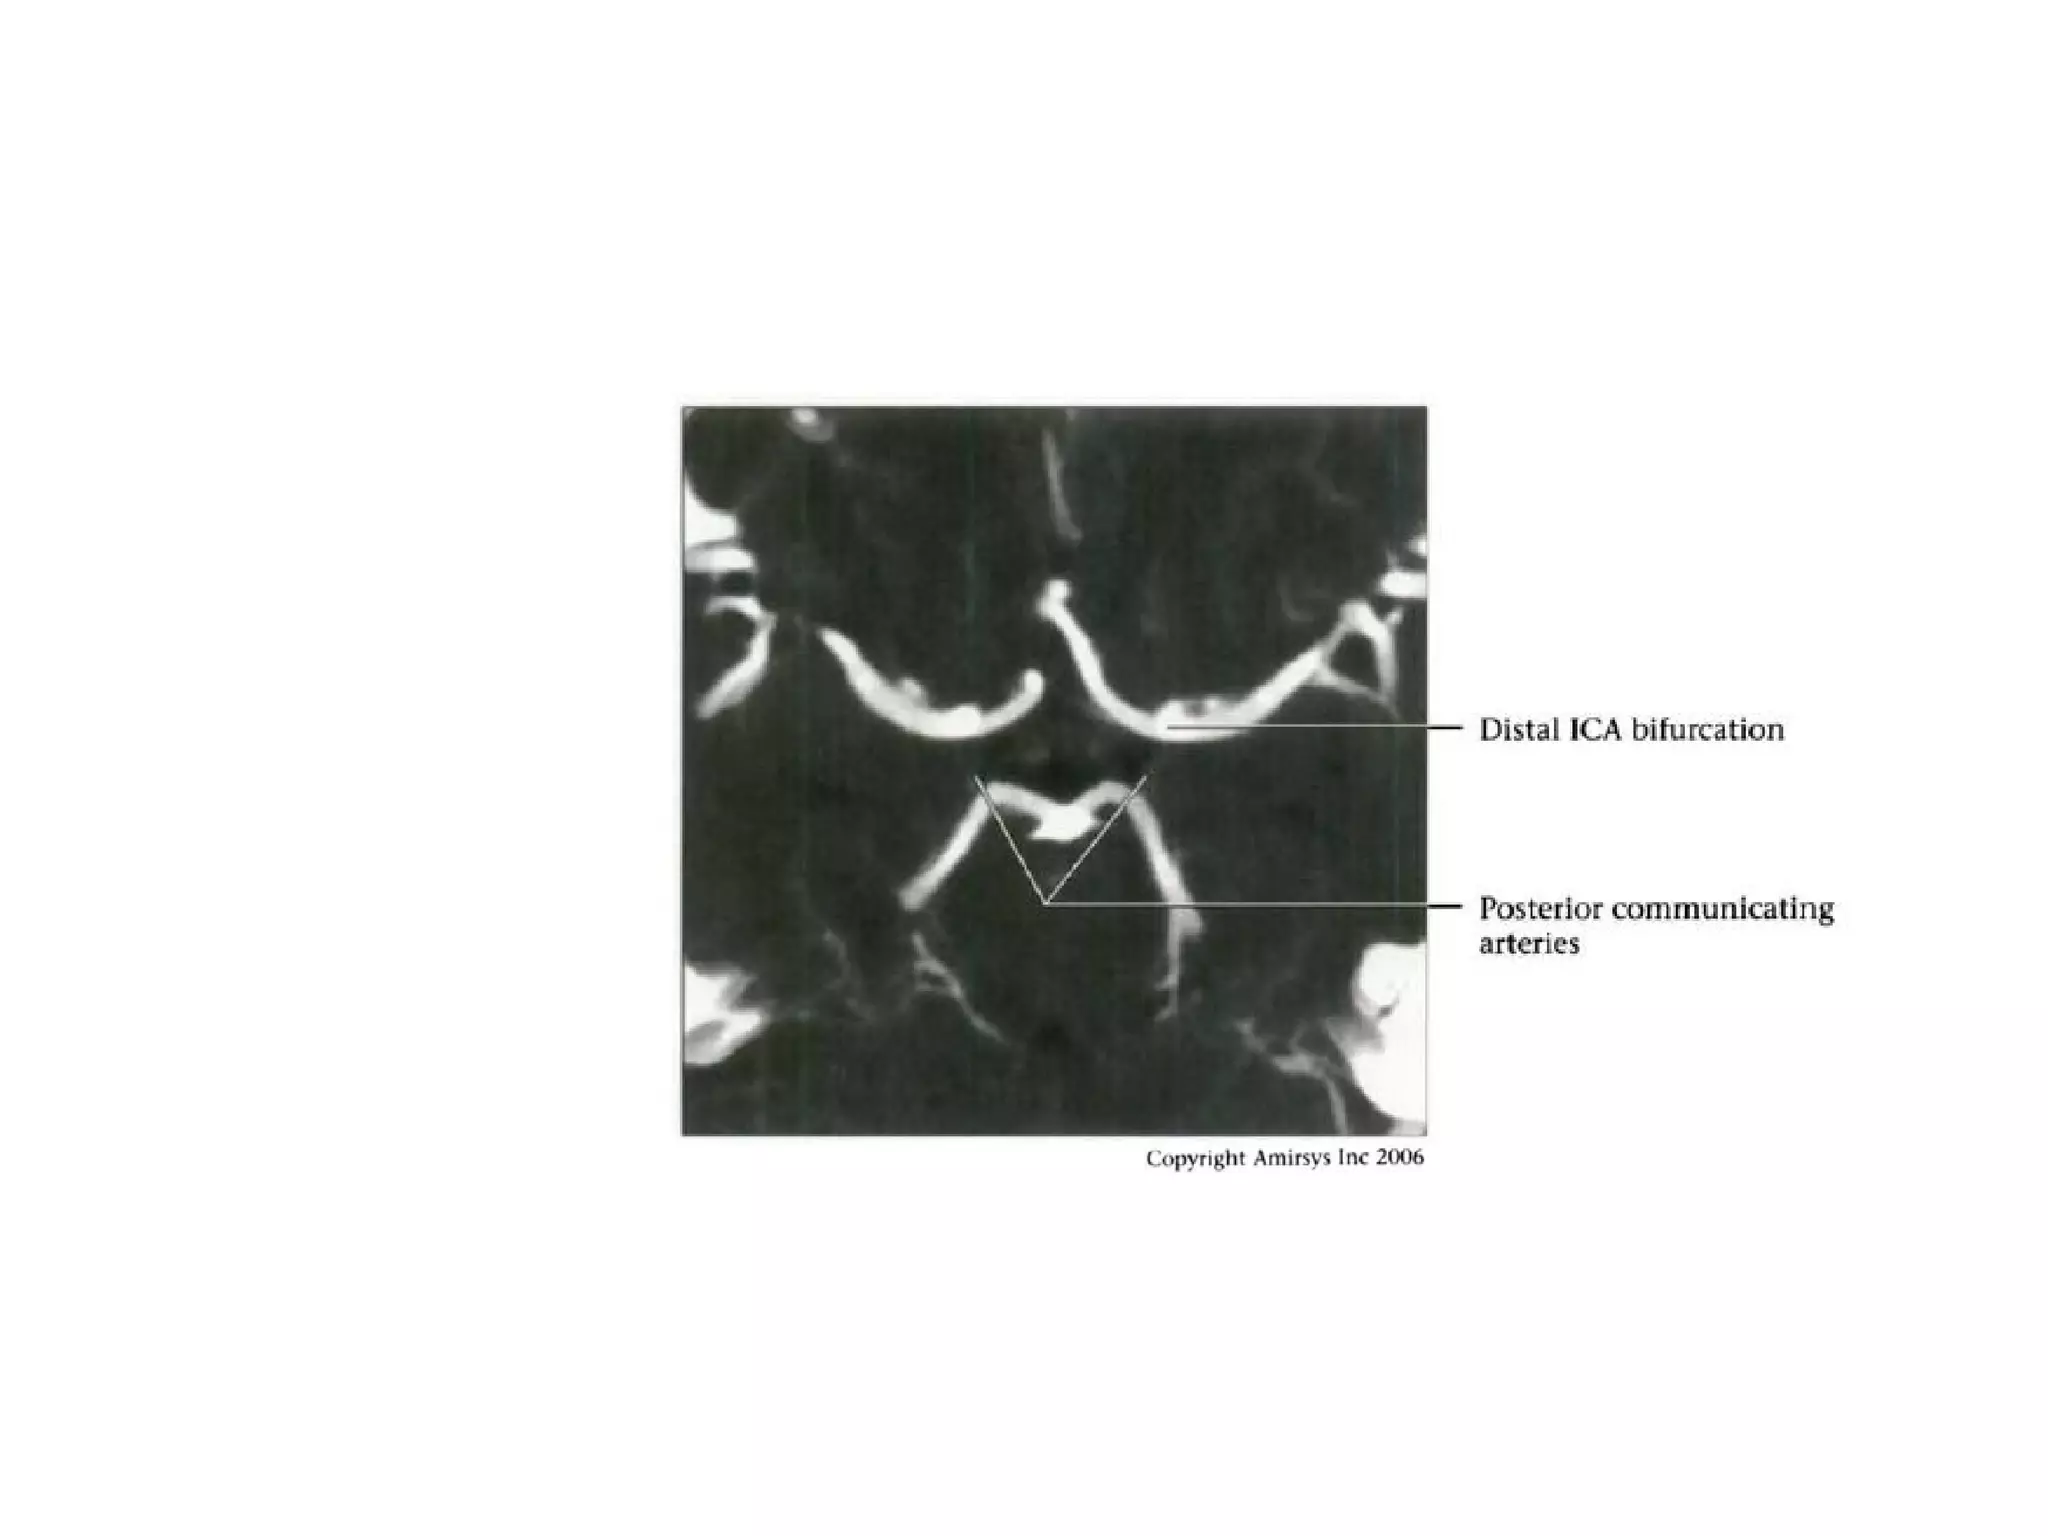

• Terminal bifurcation into ACA (smaller, medial), MCA

(larger, lateral)

Communicating (C7) segment

• Extends from below PCoA to terminal lCA bifurcation

into anterior cerebral artery (ACA), middle cerebral artery

(MCA)

• Passes between optic (CN2), oculomotor (CN3) nerves

• Major branches

- Posterior communicating artery

- Anterior choroidal artery (courses posteromedial,

then turns superolateral in suprasellar cistern; enters

temporal horn at choroidal fissure; supplies choroid

plexus, medial temporal lobe, basal ganglia,

posteroinferior internal capsule)